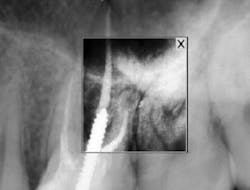

By 2:22 p.m., I was taking periapical x-rays with the gutta-percha to check my working lengths and evaluate the separated files. The x-ray showed that my access wasn’t as open as I originally thought it to be. The canal curved in two places, which caused the file separations. At this point I had two separated files—the 0.1 Twisted File (TF) file and the 15 mm hand file I had used to bypass the canal.

I proceeded to bypass the separated files with a 10 c-file. The apex locator still wasn’t giving me a reading. I was ready to obturate the canal, leaving all the extra metal as fill. Upon drying the canal with paper points, I noticed the paper point disappeared immediately toward the buccal. I took a step back to remove the buccal wall for better access. At this point, I was able to visualize the DB canal much better and was able to remove both of the separated instruments.

After obturation, it became apparent why the apex locator had given no reading for the DB canal. The foramen was located 3–4 mm away from the apex and on a curve that no file could reach. As a result of copious irrigation, the sealer was expressed from the apex.